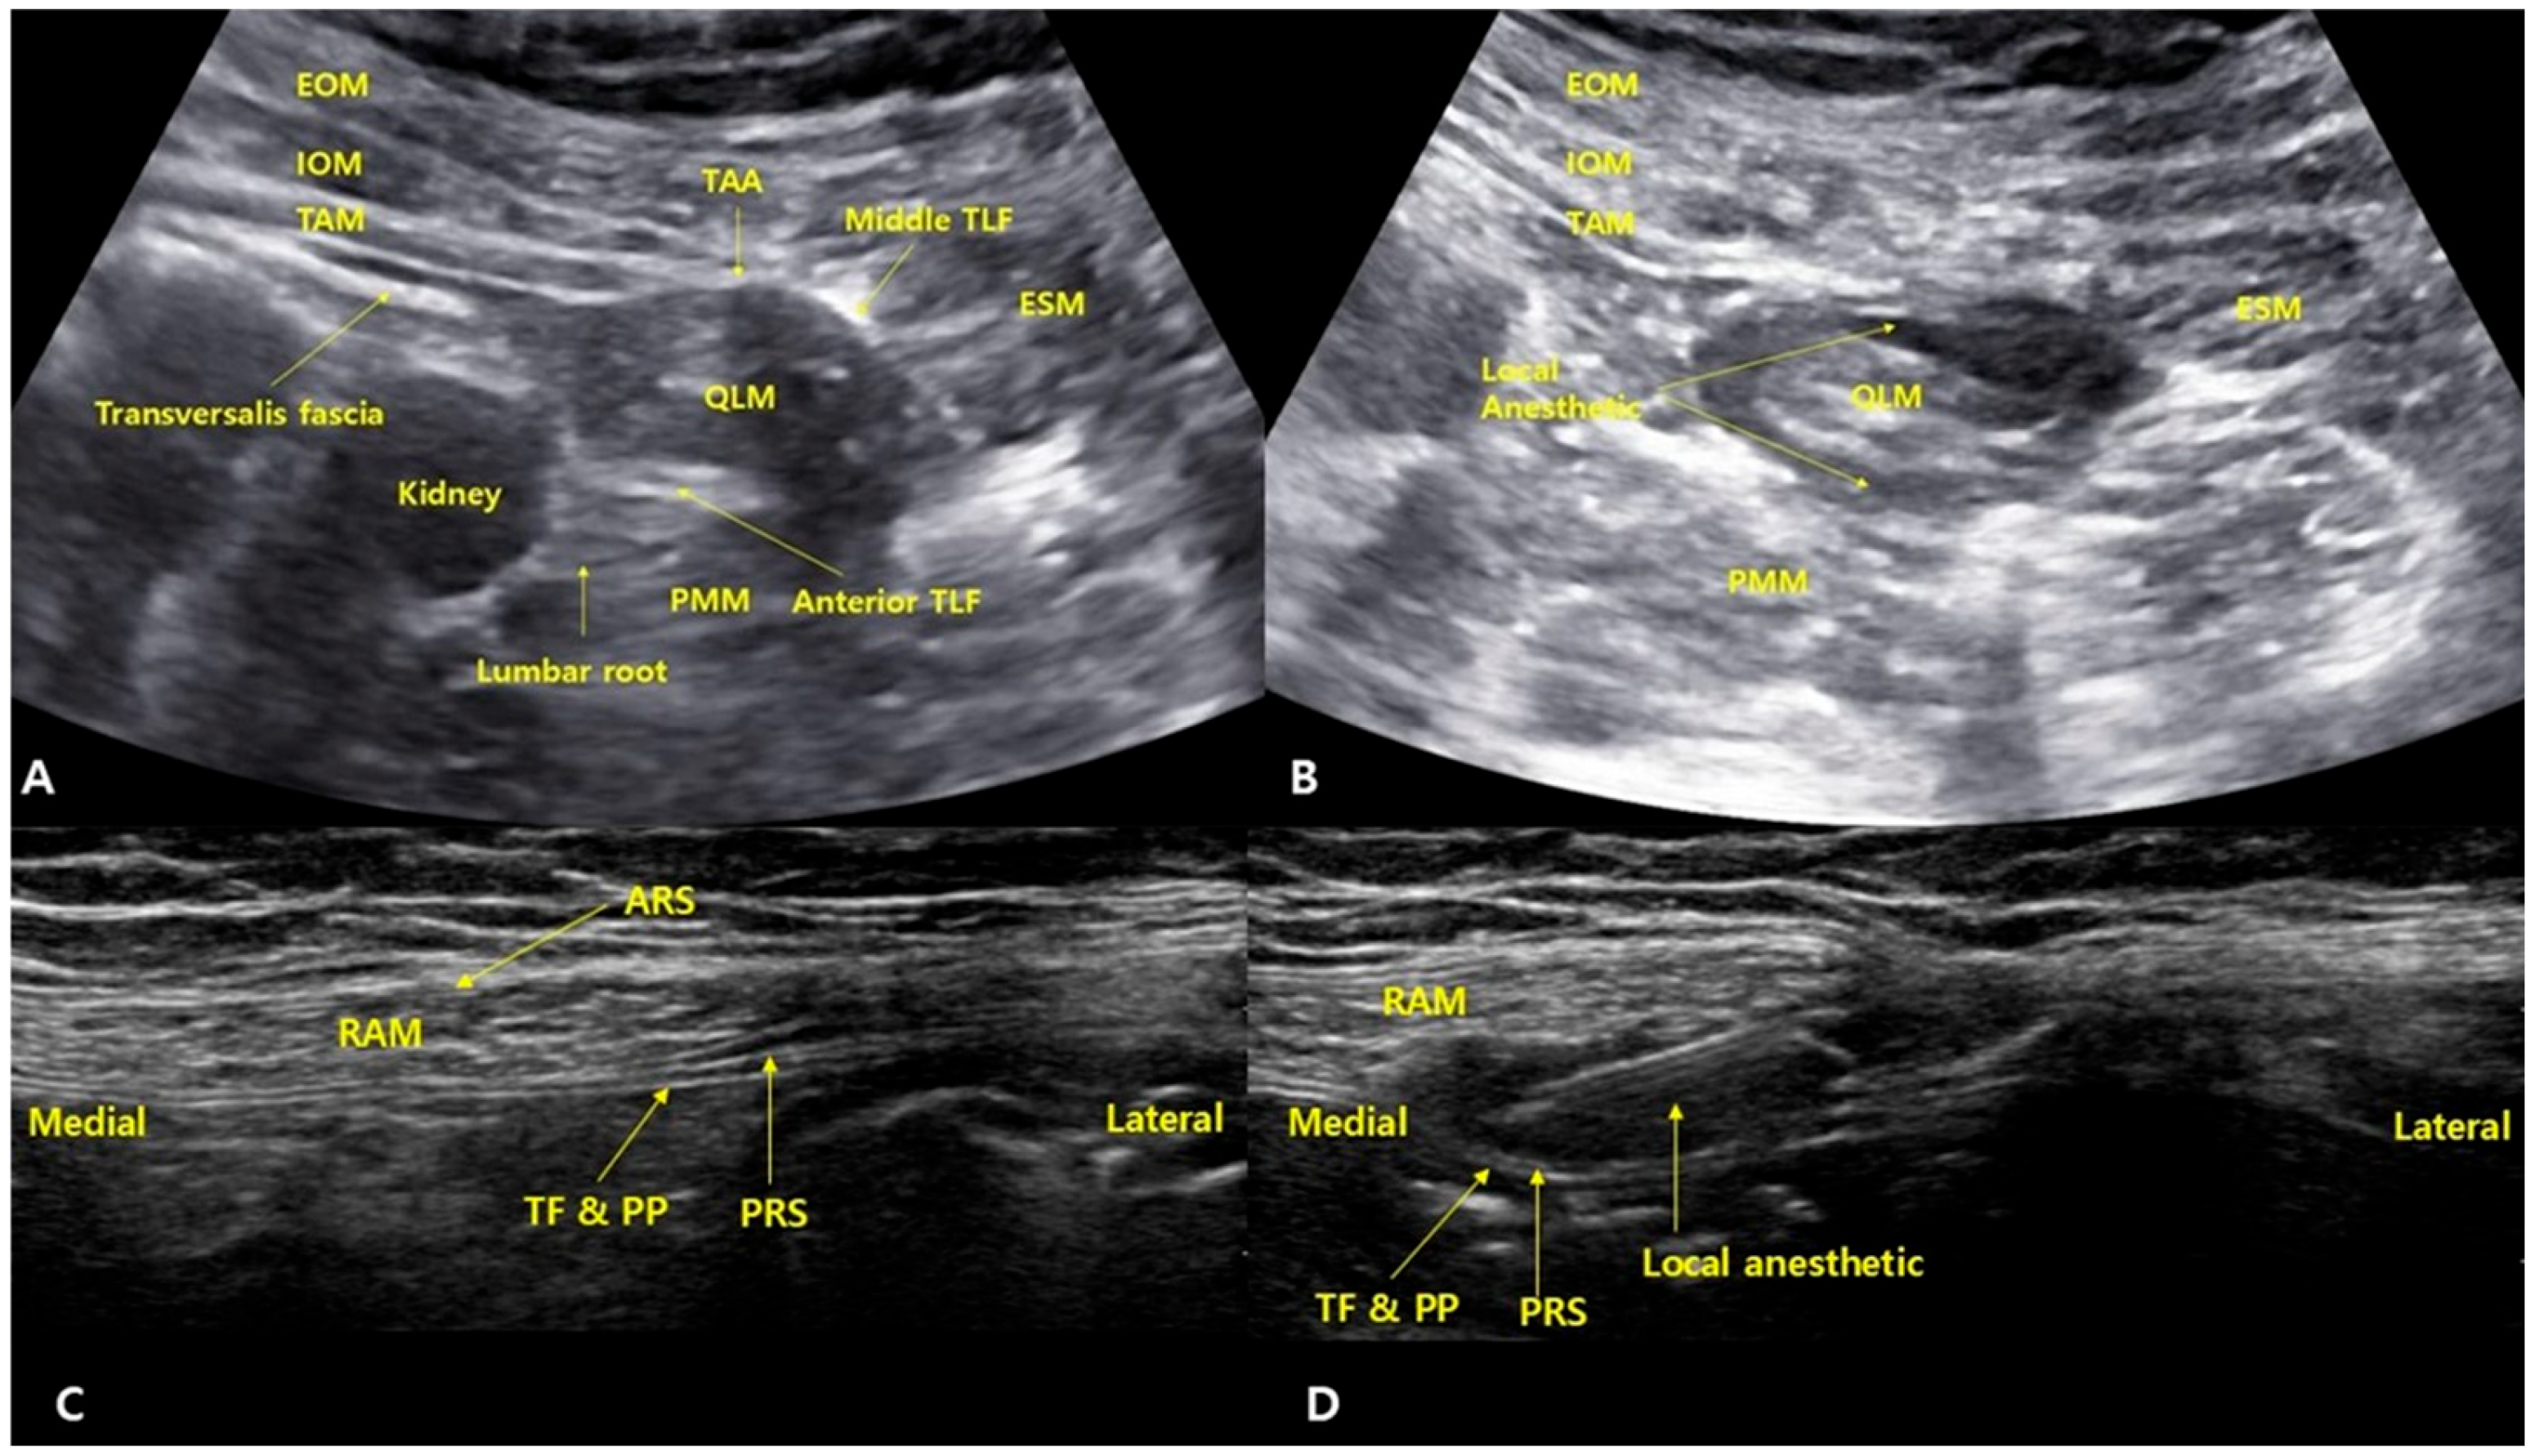

After the completion of surgery, patients were placed in a slightly tilted supine position with a folded pillow under the buttocks to create sufficient space for the ultrasound probe. A convex probe was placed along the midaxillary line and scanned posteromedially to identify the three abdominal wall muscles and the aponeurosis of the transversus abdominis. The thoracolumbar fascia (TLF) was identified, including the anterior layer surrounding the psoas major, the middle layer surrounding the quadratus lumborum, and the posterior layer around the erector spinae muscles. A 22-gauge Tuohy needle was inserted from the anterolateral aspect toward the posteromedial direction, targeting the middle layer of the thoracolumbar fascia adjacent to the lumbar interfascial triangle area. After the needle tip contacted the middle TLF, a tactile “pop” was felt as it passed through. A small volume of saline (1–2 mL) was injected to confirm that the needle tip was correctly positioned in the fascial plane between the middle TLF and the QLM. Then, 20 mL of 0.375% ropivacaine with epinephrine (5 µg/mL) was administered (Figure 1). The probe was then rotated 90 degrees to confirm that the local anesthetic had spread between the middle and anterior layers of the TLF, surrounding the quadratus lumborum muscle (QLM). The same procedure was performed on the contralateral side.

Figure 1. Ultrasound images illustrating the quadratus lumborum block (QLB) and rectus sheath block (RSB). (A) Before the injection of local anesthetic for QLB. (B) After injection, showing the spread of local anesthetic around the quadratus lumborum muscle, with visible accumulation between the middle and anterior layers of the thoracolumbar fascia. (C) Before the injection of local anesthetic for RSB. (D) After injection, the local anesthetic spreads between the posterior aspect of the rectus abdominis muscle and the posterior rectus sheath. ARS: anterior rectus sheath, EOM: external oblique muscle, ESM: erector spinae muscle, IOM: internal oblique muscle, PMM: psoas major muscle, PRS: posterior rectus sheath, QLM: quadratus lumborum muscle, RAM: rectus abdominis muscle, TAA: transversus abdominis aponeurosis, TAM: transversus abdominis muscle, TF and PP: transversalis fascia and parietal peritoneum, TLF: thoracolumbar fascia.